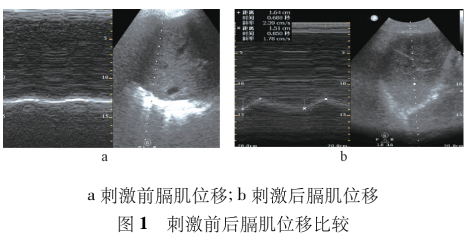

膈肌肌肉评估,7月16日患者二次插管后采用超声行膈肌形态学评估:凸阵探头在B型模式下测量膈肌位移0.92 cm(见图1a),线阵探头在M型模式下测量不同时相下膈肌厚度:呼气相为1.25 mm、吸气相为1.41 mm, 计算出DTF为12.8%,评估为膈肌功能障碍。7月17日经鼻置入食道压导管监测食道压和胃内压,计算出平静吸气下跨膈压-1.7 cmH2O,最大吸气跨膈压2.7 cmH2O,评估结果显示患者膈肌功能障碍。

采用北京雅果呼吸神经肌肉刺激仪行呼吸神经刺激,膈肌和腹肌锻炼,每日3次,每次10~15 min, 刺激电流依次递增至为5~7 mA,刺激频率为40 Hz, 刺激时间根据患者吸气时间确定,一般为1 s, 刺激频率根据患者的呼吸频率设置,使用过程发放刺激冲动时嘱患者吸气,每次刺激前后行膈肌超声检查对比,膈肌位移和增厚分数均有不同程度的增加(见图1b、图2、图3所示)。同时在膈肌刺激前后行跨膈压监测,在刺激前测出胃内压10.9 cmH2O,食道压12.6 cmH2O,跨膈压为-1.7 cmH2O,最大吸气胃内压为14.8 cmH2O,最大吸气食道压为12.1 cmH2O,最大吸气跨膈压为2.7 cmH2O,刺激后测出胃内压16.4 cmH2O,食道压11.8 cmH2O,跨膈压为4.6 cmH2O,最大吸气胃内压为21 cmH2O,最大吸气食道压为8.6 cmH2O,最大吸气跨膈压为12.4 cmH2O,每次刺激前后行跨膈压监测,患者跨膈压有不同程度的增加(见图4)。